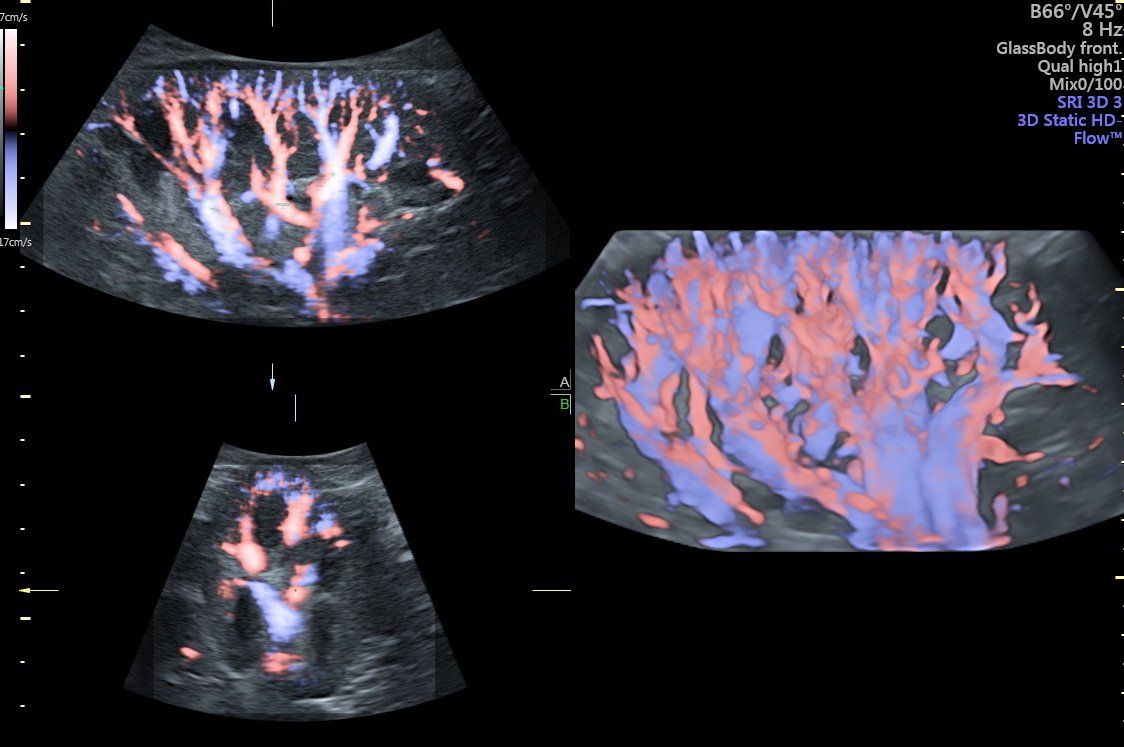

La diagnostica Eco-Color-Doppler si rende utile sia nello studio degli organi interni sia nella valutazione dei distretti vascolari arteriosi e venosi. Gli esami eco-color-Doppler sono indicati per lo studio delle carotidi/tronchi sovra-aortici (patologie cerebro-vascolari e cardiologiche), per la valutazione dell’aorta addominale (aneurismi, dissecazioni), per la valutazione delle arterie degli arti inferiori (arteriopatia ostruttiva, diabete), per la valutazione delle vene degli arti inferiori (insufficienza venosa, varici arti inferiori).